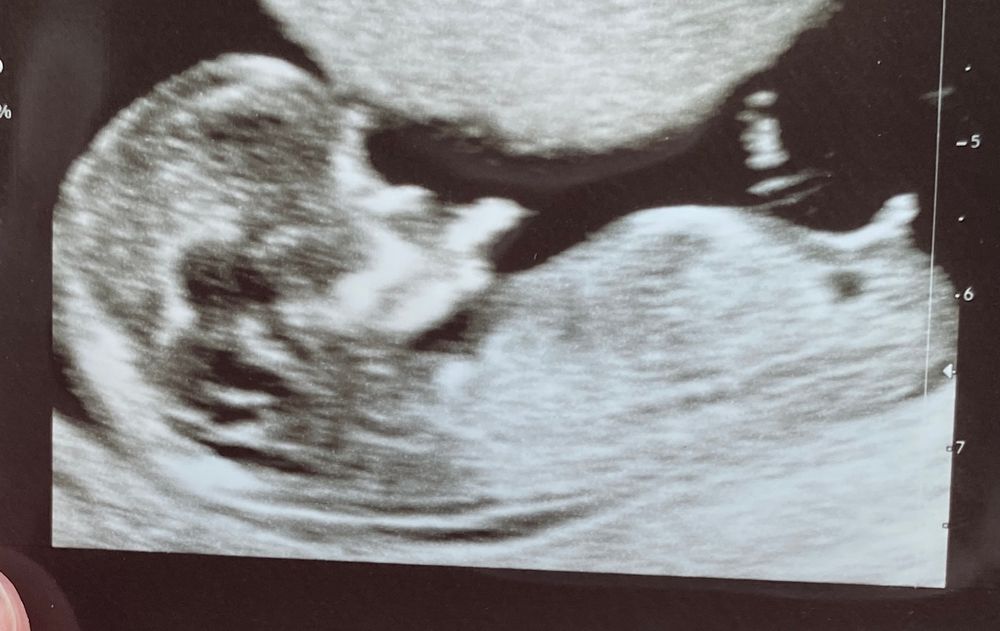

Здравствуйте. Девочки, как думаете кто? Похож ли на мальчика? Могут ли быть ошибки по определению по

Пол малыша

Думаю девочка,у мальчика бугорок 90 градусов а тут 60